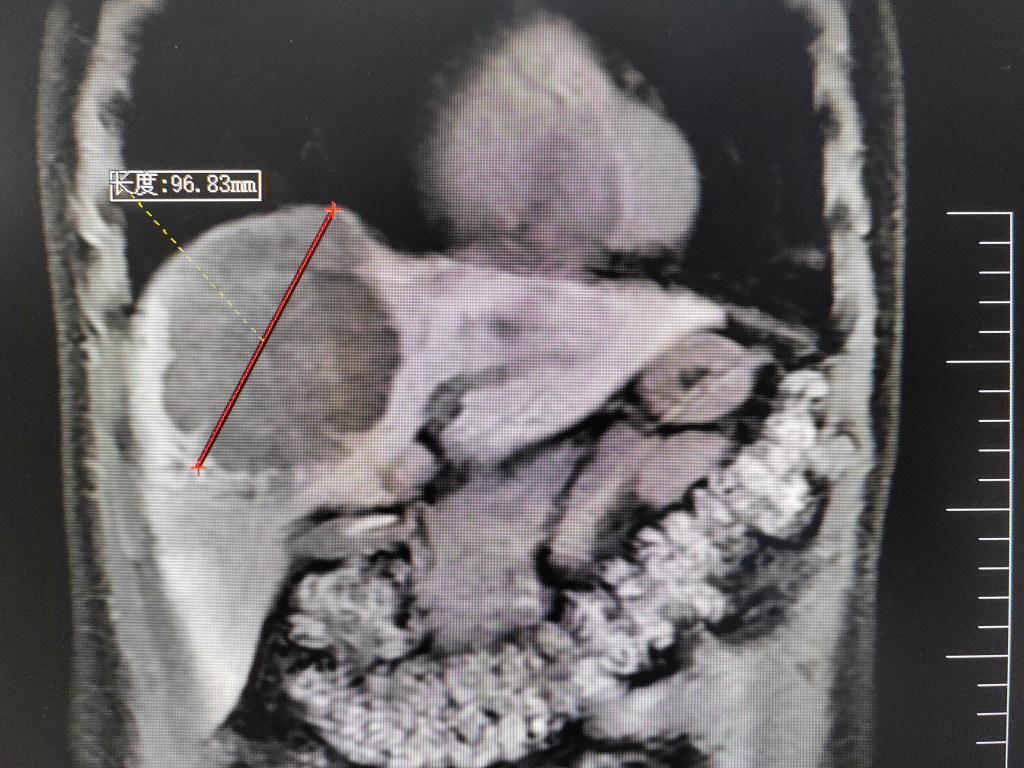

35岁的郑先生,今年3月份出现“右上腹痛”症状,外院行肝胆B超检查提示“肝占位”。患者遂至肿瘤医院肝胆胰外科古松钢副主任医师门诊就诊。入院后查甲胎蛋白为10013.000 ng/mL,腹部增强CT及普美显增强MR检查均显示:肝S4/8肿块,大小约10×8cm,考虑原发性肝癌,伴门脉右支癌栓。

腹部增强CT及MR检查提示肝中叶巨块型肝癌伴门静脉右支癌栓